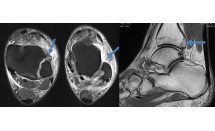

Dans les lombosciatiques et les lombo-cruralgies résistant au traitement médical bien conduit, l'IRM est l'examen de première intention. Dans certains cas, on observe une image intracanalaire ou foraminale à distance du disque intervertébral de signal variable en T2 (fig. 1). Dans la plupart des cas, cette image correspond à un fragment herniaire exclu.